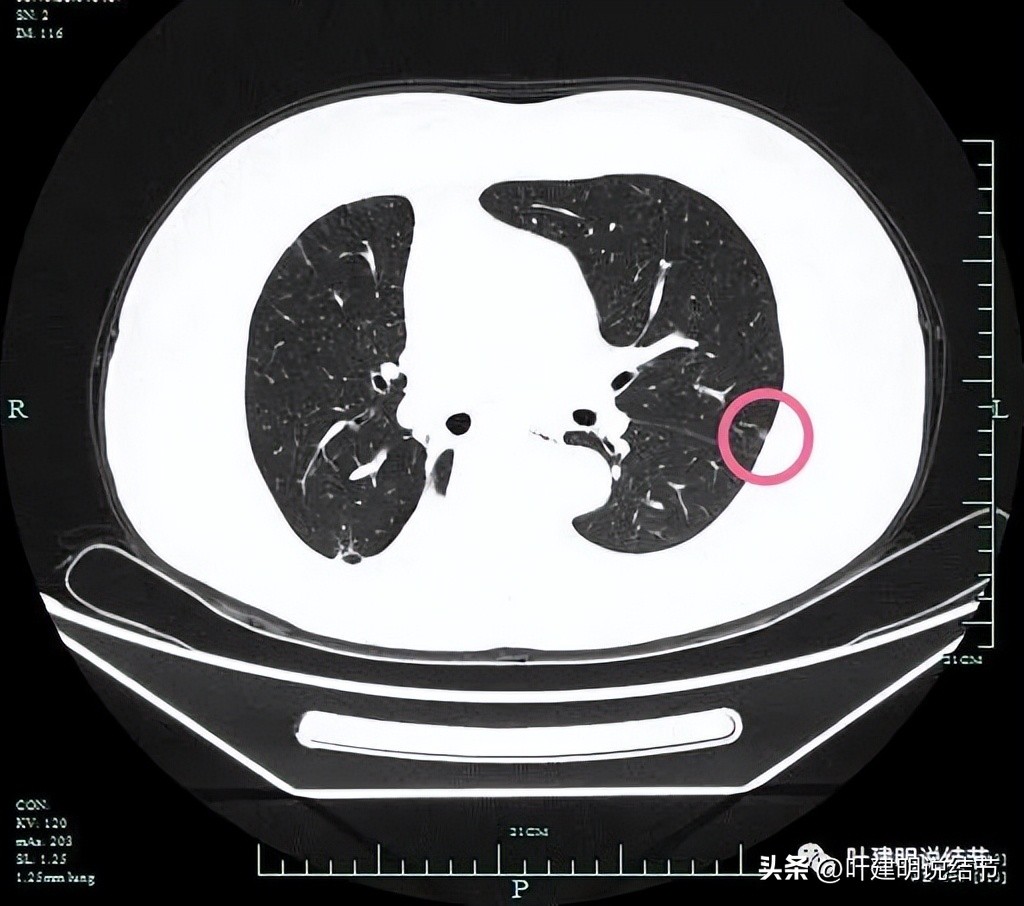

左上病灶1:磨玻璃密度,靠胸壁侧密度较高,有实性成分。

胸膜似略有影响,整体轮廓较清。

密度偏高。

瘤肺边界清楚。

左上病灶2:胸膜下微小磨玻璃结节,也是轮廓较清的。